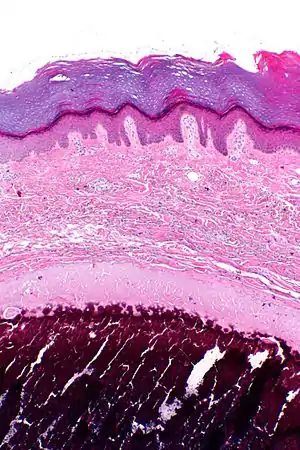

| Micrograph of calcinosis cutis. The calcification is purple (bottom of image). H&E stain. | |

Calcinosis cutis is a type of calcinosis wherein calcium deposits form in the skin. A variety of factors can result in this condition. The most common source is dystrophic calcification, which occurs in soft tissue as a response to injury. In addition, calcinosis is seen in Limited Cutaneous Systemic Sclerosis, also known as CREST syndrome (the "C" in CREST).[1] In dogs, calcinosis cutis is found in young, large breed dogs and is thought to occur after a traumatic injury.